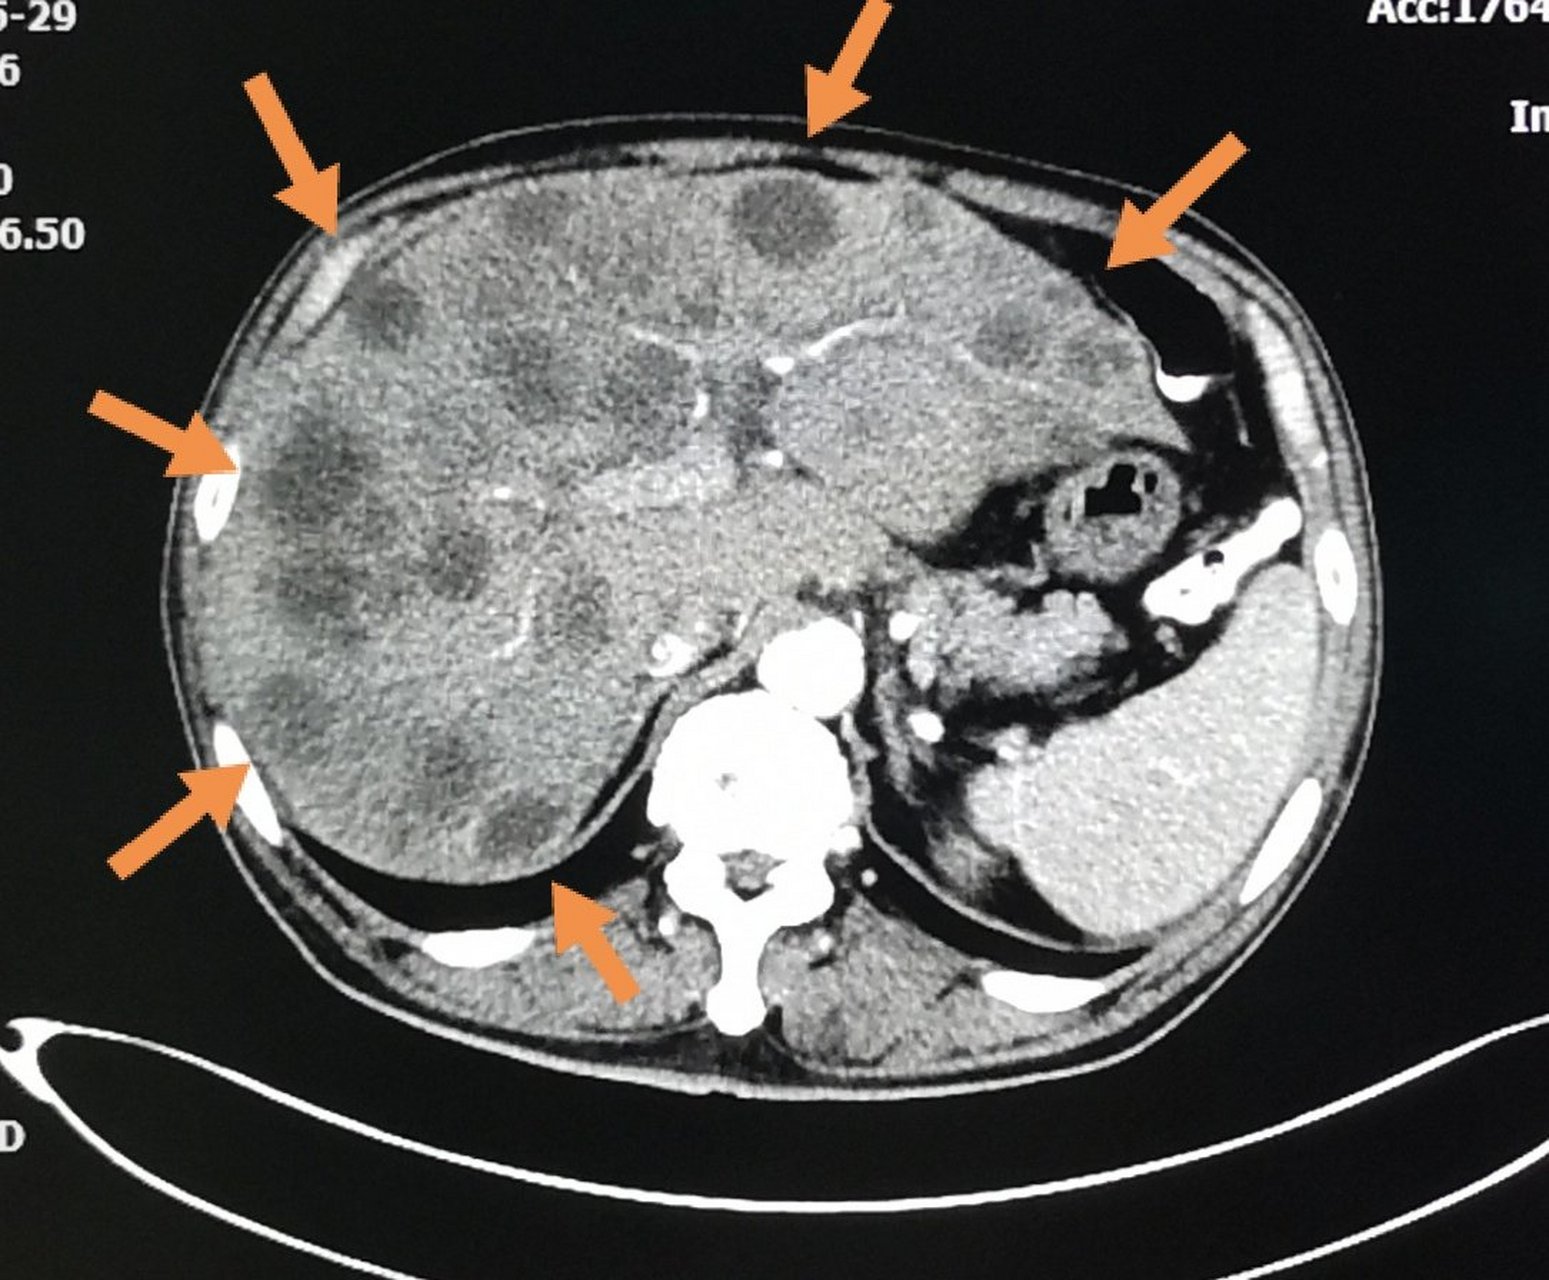

66岁老人,突然不爱吃饭3天,肚子胀, ct发现肝脏长了几十个圆形转移瘤